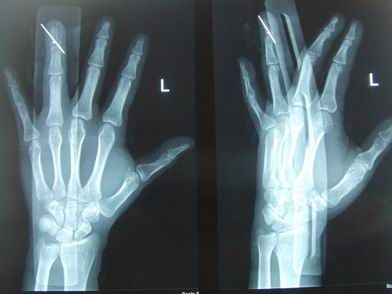

指骨骨折手法复位 - 骨科专业讨论版 -丁香园论坛

图片尺寸2448x3264